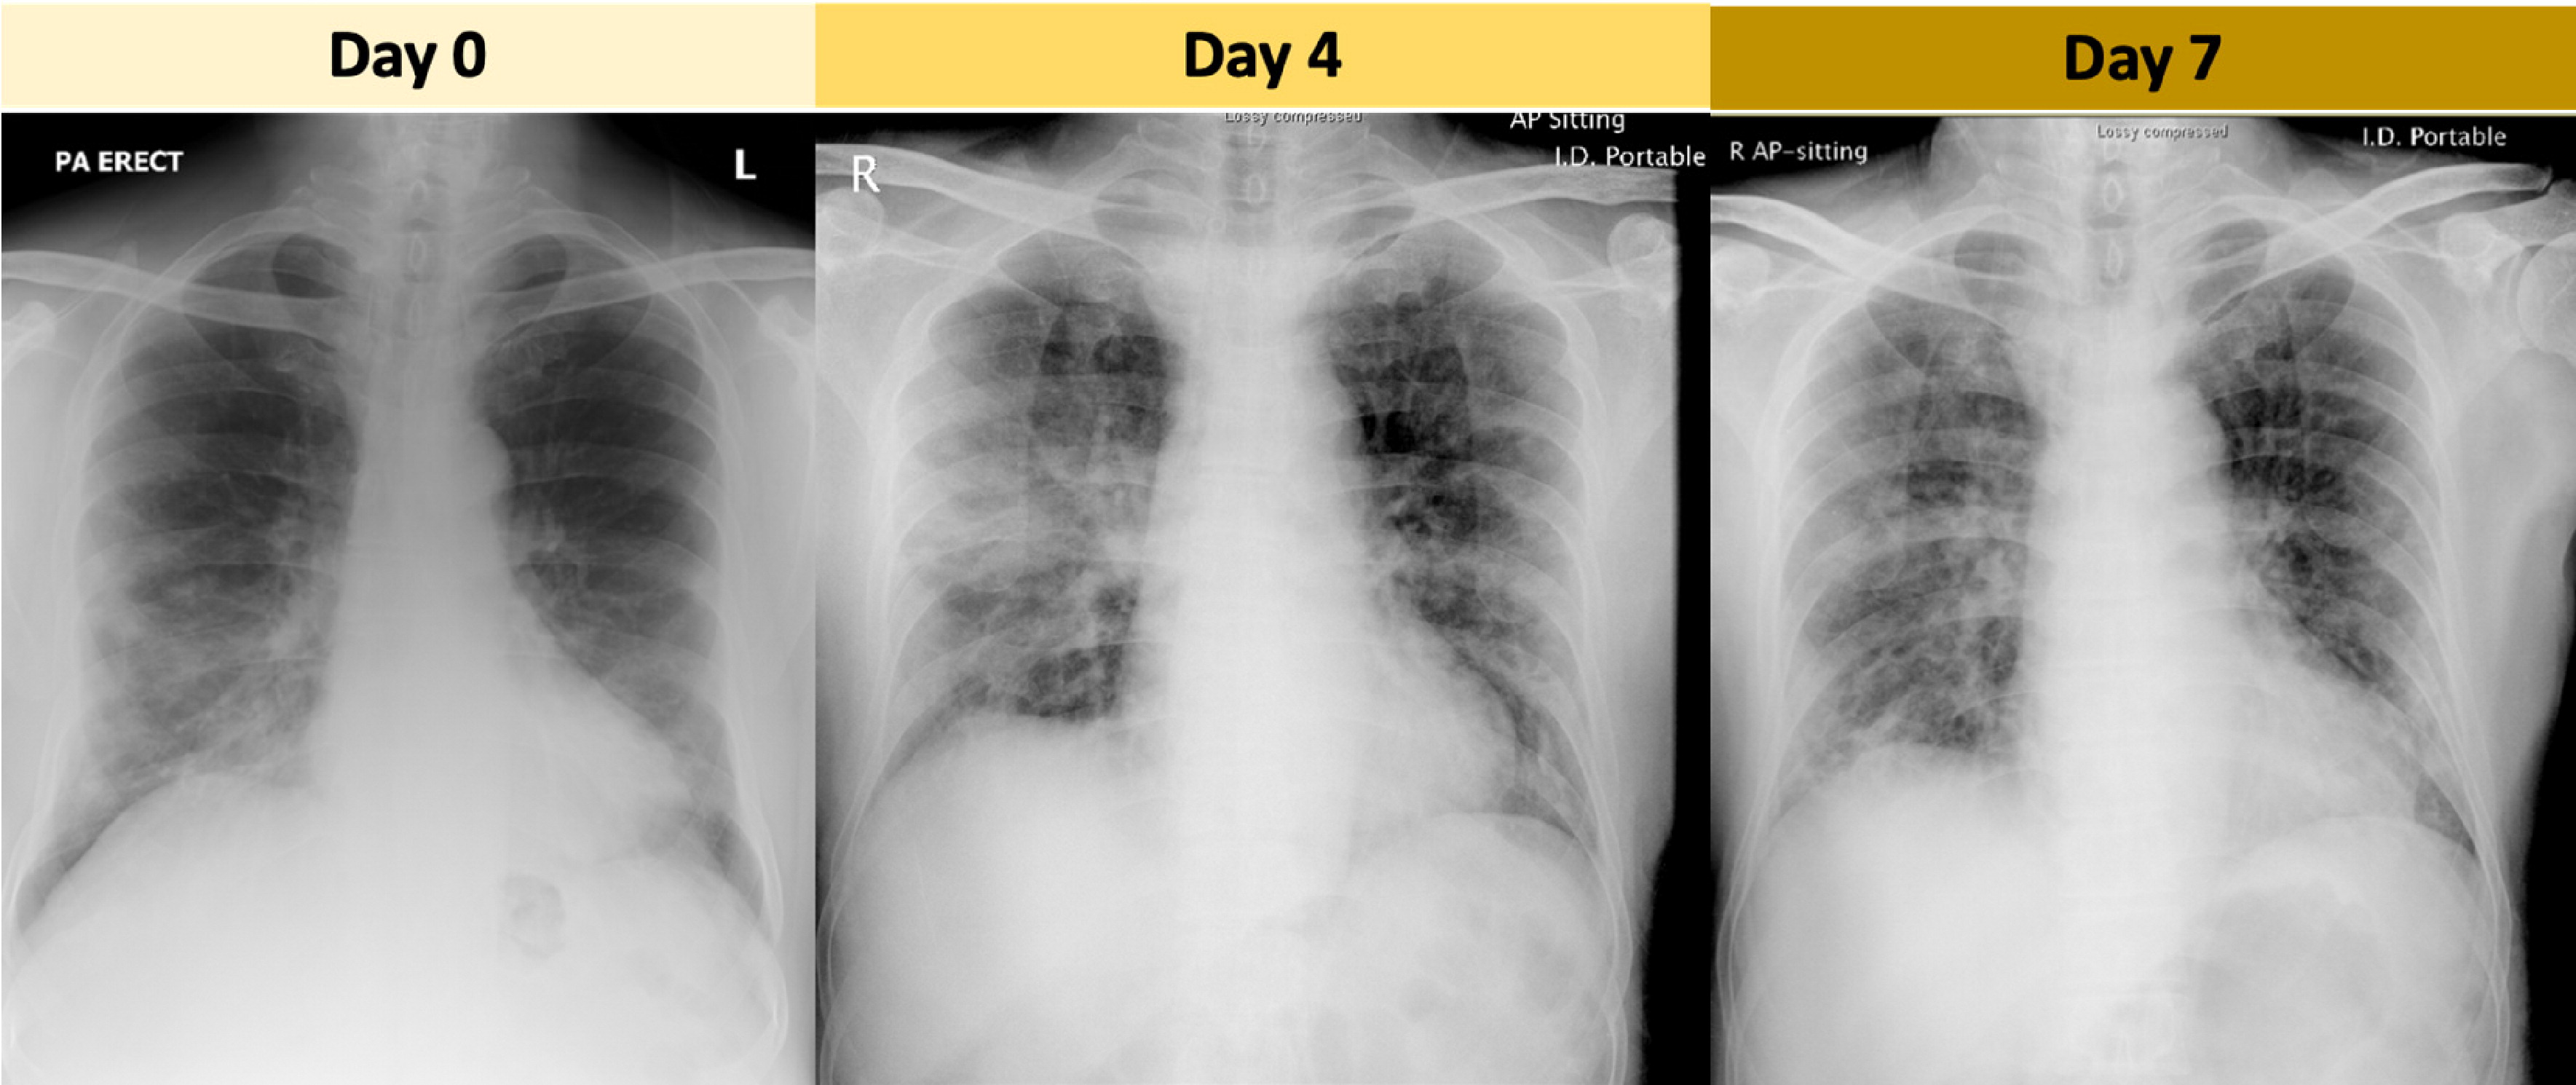

ये तस्वीरें रेडियोलॉजिकल सोसाइटी ऑफ नॉर्थ अमेरिका (RSNA) ने जारी की है। फेफड़ों के एक्स-रे और सीटी स्कैन से सामने आया है कि पीड़ितों के फेफड़ें चिकने और गाढ़ी बलगम (म्यूकस) से भर जाता है। इसके कारण पीड़ित व्यक्ति की सांस घुटने लगती है क्योंकि उसके फेफड़ों में हवा जाने के लिए कोई जगह ही नहीं बचती।

इस 3D इमेज के बनने के बाद डॉक्टर एक्स-रे और सीटी स्कैन से ऐसे मरीजों की बहुत जल्दी पहचान कर पाएंगे जो गंभीर रूप से संक्रमित हैं और जिन्हें तुरंत सबसे आइसोलेट करने की जरूरत है। चीन के वुहान शहर से फैला कोरोनावायरस (कोविड-19) अब तक 111 से ज्यादा देशों में फैल चुका है। दुनियाभर में 4,640 लोग मारे गए हैं। एक लाख 26 हजार से ज्यादा लोग संक्रमित हैं।